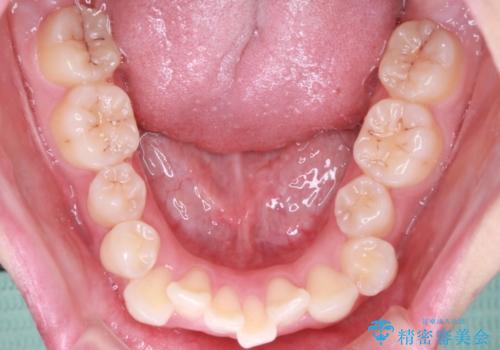

【抜歯インビザ】前歯の凸凹をなおしたい

- 前歯の凸凹を主訴に来院されました。

前歯はあまり下げる必要がなかったため、上下左右の第二小臼歯抜歯を行う治療計画としました。

途中、臼歯の近心傾斜を認めましたが、追加アライナーを使用することでリカバリーを行いながらインビザラインのみで治療を完了することができました。